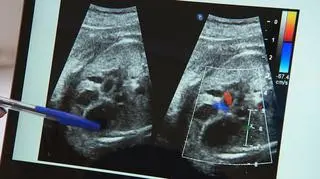

Operacja serca w łonie matki

Badanie USG u dzieci